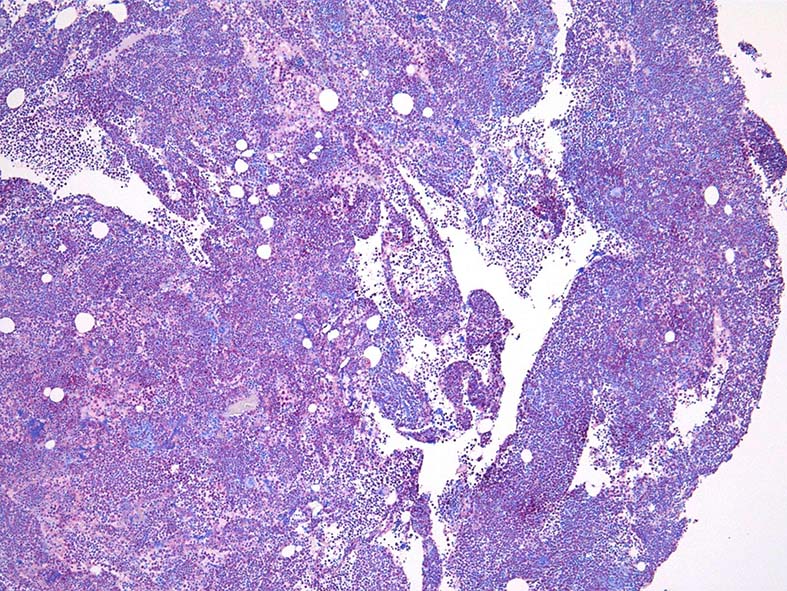

骨髄組織所見 (thumbnailのクリックで大きな画像がみられます)

Fig.01: hypercellular marrow. ASDで赤染する細胞の増加=granulopoietic hyperplasiaがある.

Fig.02: 幼若な顆粒球が増加している. 赤芽球は散在しており血島は不明瞭である. 過形成髄なのにFig.02に成熟大型巨核球はみられない.

Fig.03: granulopoietic hyperplasia. 成熟顆粒球の増加もある.